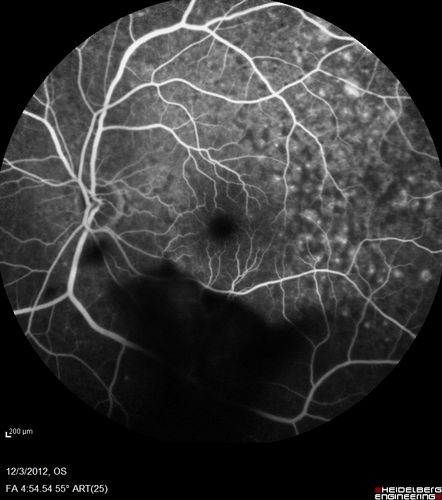

Uveitis - Retinitis - Vasculitis - possibly Syphilitis

74-year-old man 12-3-12 visit.  2 months ago noticed vision loss, first in the right eye than the left.   He is getting tired easily.  He can’t walk for a long distance.  He has lost five pounds within the last month. He also had a severe itchy episode, but not quite a rash a few days ago, which went away after he took a shower.  FTA-ABS is positive but a spinal tap, which was negative.  OD 1/200,  OS 20/63.